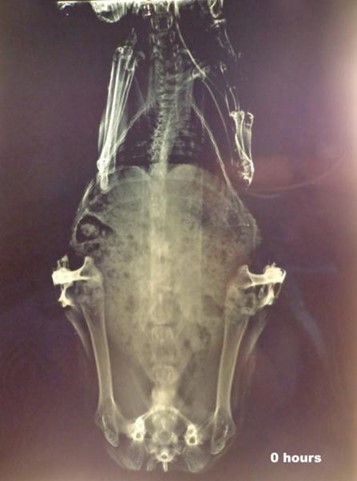

X-ray studies revealed that the microspheres remained in the stomach for the first 2h as shown in fig. (7). Microspheres get released from the capsule shell by dissolving the gelatin shell and distributed in the small intestine as observed in the fig. (8).

Fig. 6: X-ray image before drug administration